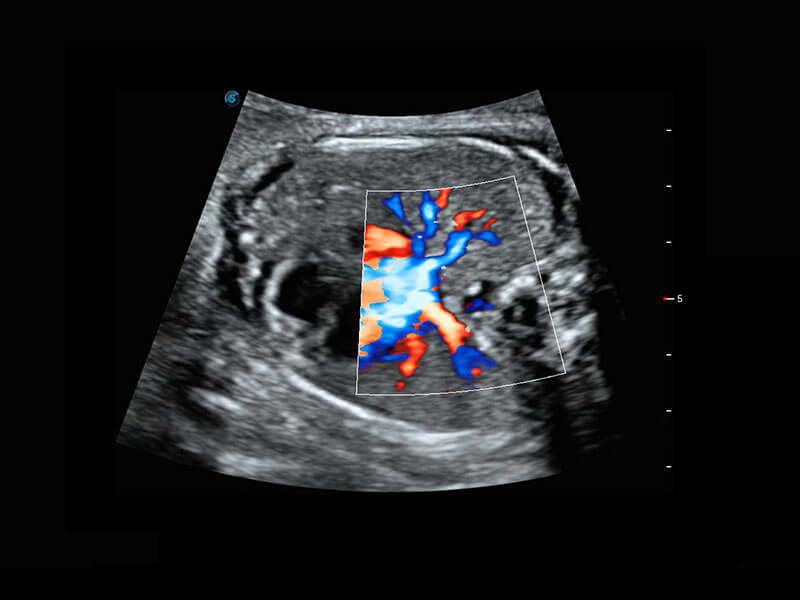

• 胎儿体循环

• 四腔心血流